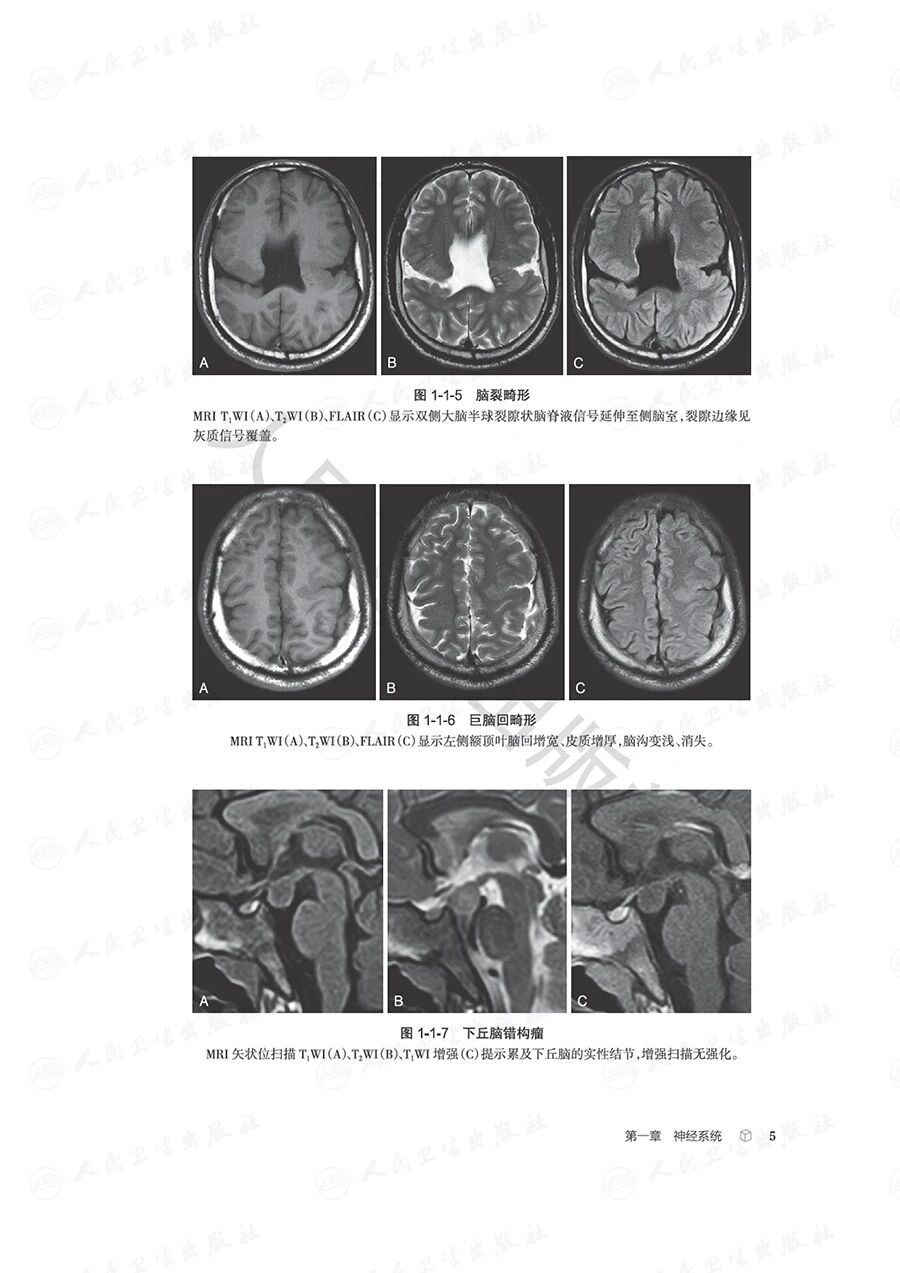

本书紧扣影像科医师日常执业场景,依托中华医学会放射学分会青年学组“青影智慧-影像诊断思维系列培训课程”的核心体系,全面汇总并梳理了临床影像诊断中高频出现的近300个典型征象,覆盖神经系统、头颈五官、呼吸、心脏大血管、乳腺、消化、泌尿、生殖、骨关节等九大核心诊疗领域。

全书以影像征象为核心切入点,深入剖析并提炼各征象的特异性影像学表现,辅以典型病例图像直观佐证;借助思维导图清晰可视化征象分析与诊断推导的完整脉络,同步融入鉴别诊断的关键要点及适配疾病谱系。通过层层拆解、去芜存菁的解析方式,完整呈现从影像征象识别到疾病确诊的全链条思维推演过程,为影像科医师提供极具参考价值的诊断思维范式。

本书旨在为医学专业人士提供系统化的影像诊断思维框架,涵盖了全身各个器官系统的常见疾病。每个章节不仅详尽介绍了各类疾病的影像学特征,还配有诊断思维树和鉴别诊断疾病谱,旨在帮助读者快速而准确地进行影像诊断。这种结构化的方法将使读者在处理复杂病例时更加得心应手。